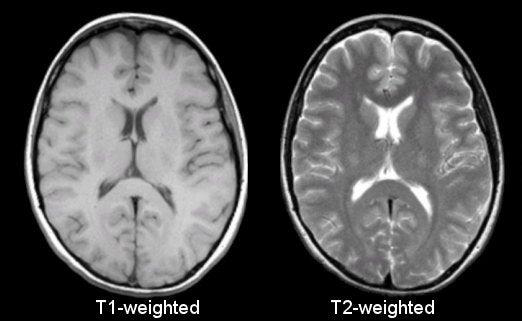

Magnetic Resonance Imaging (MRI) allows the density of nuclei in the tissue, particularly hydrogen found in water, to be imaged. The main advantages of MRI lie in the excellent soft tissue contrast it provides, the absence of absorption and shadow artefacts caused by the presence of bones and also the absence of ionising radiation required for CT/radionuclide methods. The intrinsic contrast of the MR signal can be programmed to reflect proton density and different relaxation effects of the tissue. It is emerging as an important tool for pre-operative planning because of its safety, versatility and the high-quality images it produces that allow accurate and reproducible quantification of structure and function such as blood flow and perfusion

Figure 16:MRI scans of a head, demonstrating the same anatomy but imaged using different pulse sequence. Image courtesy of Prof. Terry M. Peters at Robarts Research Institute, Canada.